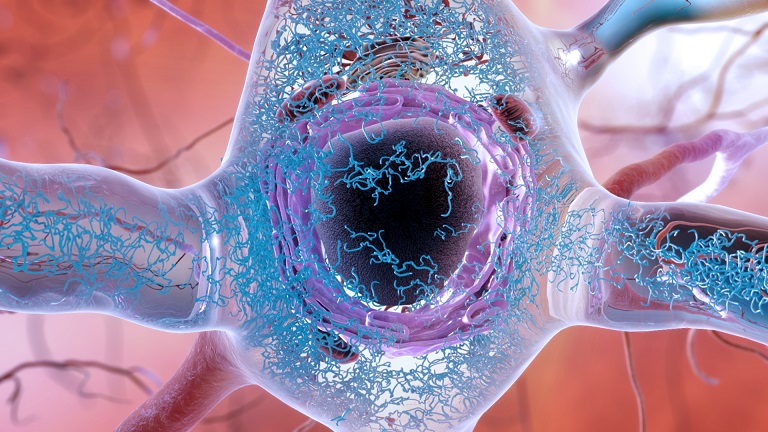

Leer másDescubren diferencias entre las neuronas humanas y de otros mamíferos

Las neuronas humanas tienen un número de canales iónicos mucho menor de lo esperado, en comparación con las neuronas de...